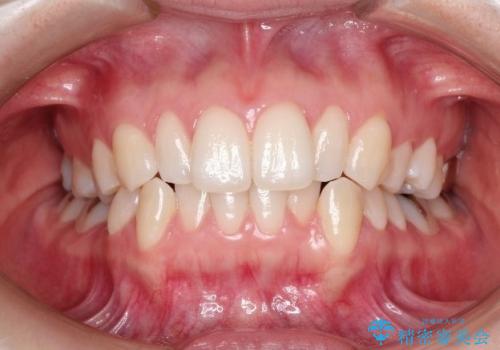

抜歯なし/インビザラインによるマウスピース矯正にて治療を行いました。

内側に入り込んでしまっている歯を出してくることに非常に時間がかかりましたが、一度歯を歯茎の方へ押し込みそして前へ出してくる2段階の治療を行いました。